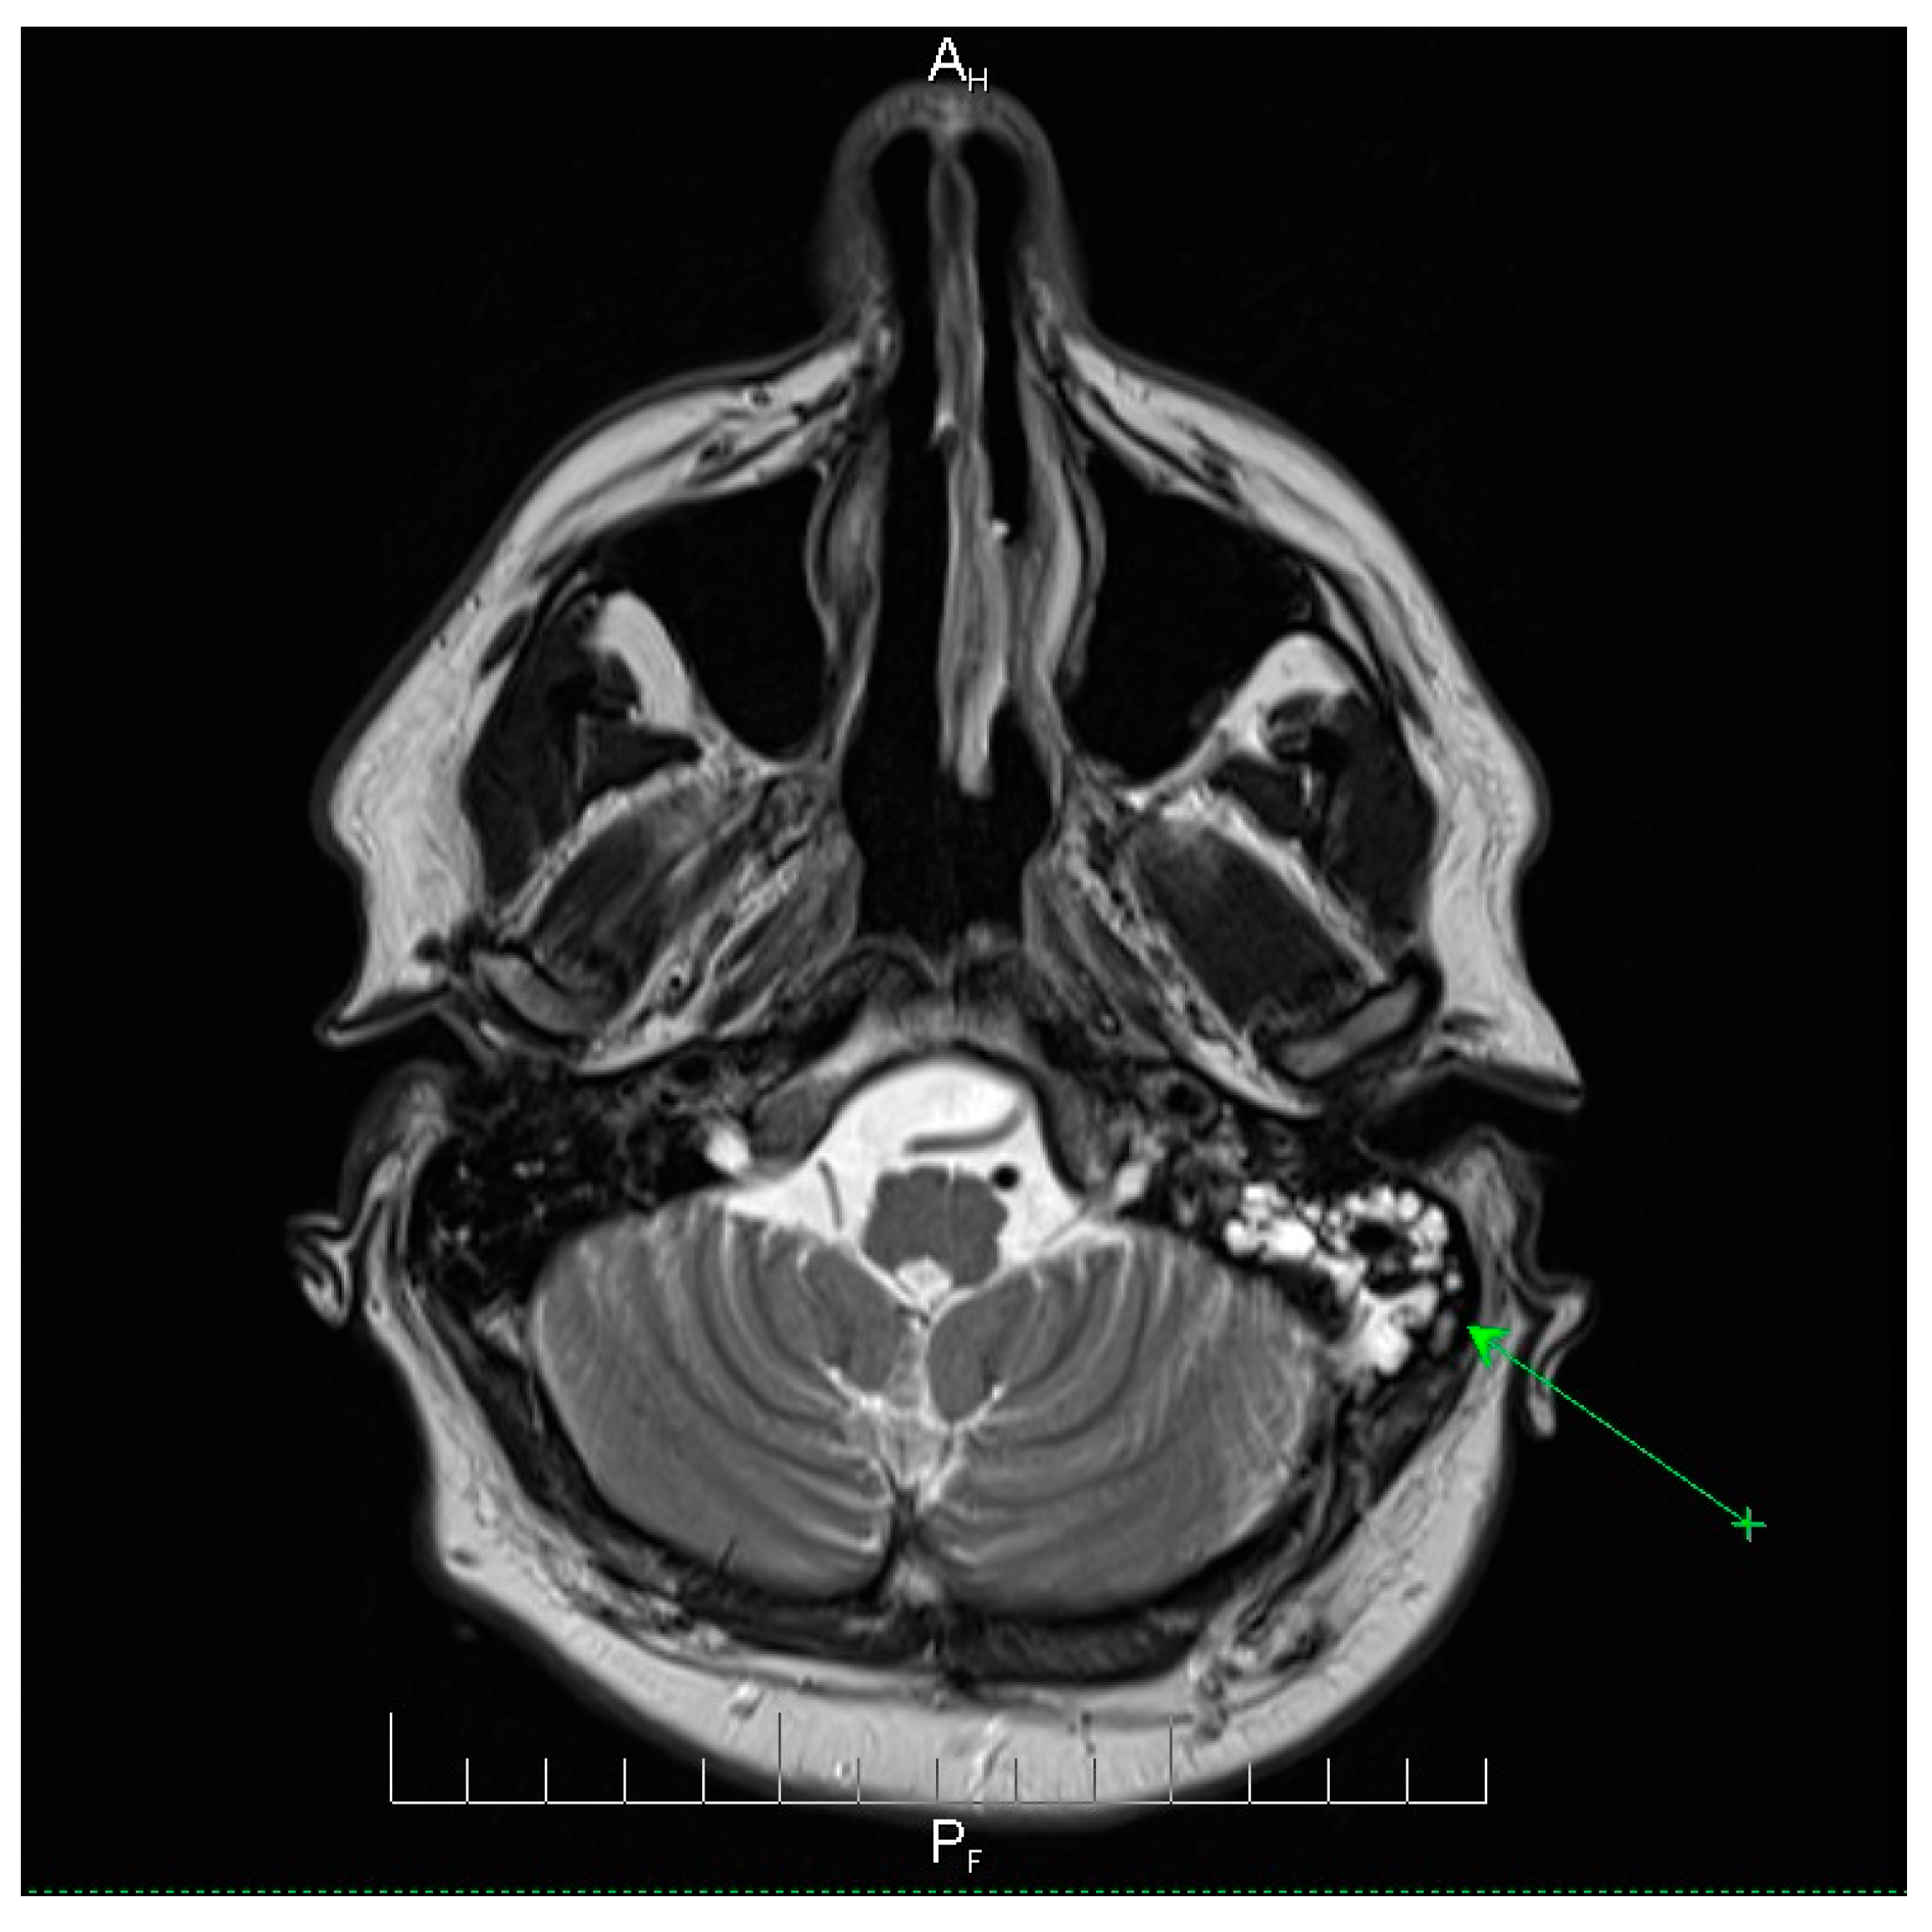

Neuroimaging revealed mild ethmoidal/sphenoidal sinus opacification and left mastoid air cell involvement without evidence of parenchymal lesions or venous sinus thrombosis (Figure 1, Figure 2 and Figure 3). Coronal and axial T2-weighted MRI sequences revealed para-fluid collections within the left mastoid air cells extending toward Citelli’s angle (Figure 1, Figure 2 and Figure 3), consistent with an otogenic focus and a possible contiguous route for intracranial spread.

Figure 3.

Axial T2-weighted MRI scan demonstrating the post-septoturbinoplasty reduction status on the right. Mild inflammatory changes were observed in the mucosa of the maxillary sinuses, predominantly on the left side, with less pronounced involvement of the ethmoidal cell system. No evidence of acute intracranial pathology or parenchymal lesions was observed. These findings indicate residual postoperative changes and mild sinonasal inflammation, providing context for the patient’s clinical presentation and helping to differentiate postoperative alterations from active infectious processes. AH = anterior-head. PF = posterior- foot. Axial T2-weighted MRI scan demonstrating the post-septoturbinoplasty reduction status on the right. The green arrow indicates a focal area of mucosal thickening and fluid signal within the left maxillary sinus, consistent with mild inflammatory changes, with less pronounced involvement of the ethmoidal cell system. No evidence of acute intracranial pathology or parenchymal lesions was observed. These findings indicate residual postoperative changes and mild sinonasal inflammation, providing context for the patient’s clinical presentation and helping to differentiate postoperative alterations from active infectious processes.